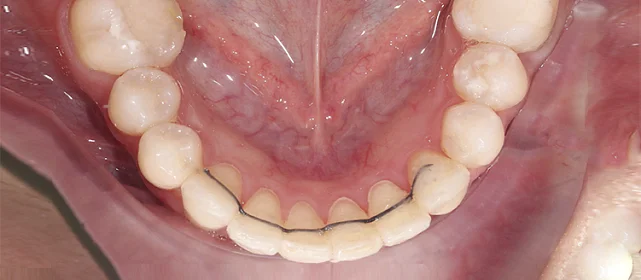

Зубы выровнены, скученность устранена, линия смыкания нормализована. Установлены несъёмные ретейнеры на обе челюсти, сняты слепки для ретенционных кап.

Решение: Поставили элайнеры Click на обе челюсти. Начали с 32 кап, но случай потребовал три дозаказа: 30, 10 и 10 кап — итого 82 капы за 30 месяцев. Количество дозаказов объясняется и сложностью случая (скученность плюс деформация кривой Шпее), и тем, что контрольные визиты были реже обычного из-за проживания за границей. Тем не менее результат достигнут: зубы ровные, смыкание в норме. На ретенцию пациентка приехала отдельно — зафиксировали ретейнеры на обе челюсти, сняли слепки для ретенционных кап.